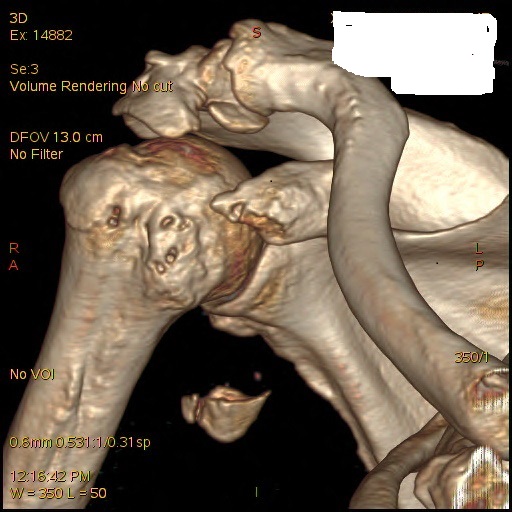

CORACOID FRACTURE

Very interesting patient seen today with a fracture of the coracoid after a fall. The coracoid is the origin of part of the biceps muscle. The fragment was displaced distally because of traction of the biceps. He had some nerve irritation initially, but this cleared. Though surgery is advocated by many he and I decided to manage it non-operatively as he is elderly and Covid-19 is a concern now. Look at this impressive picture below